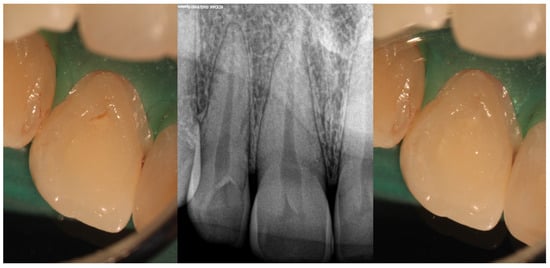

- Type II

| Type II | Moderate to high risk of pulp involvement | CBCT recommended to assess depth and pulp communication | Preventive sealing or minimally invasive restoration If pulp compromised, vital pulp therapy or root canal treatment depending on health state of pulp | Good to fair prognosis if depth is within coronal third and detected early Radiographic follow-up needed to monitor healing |